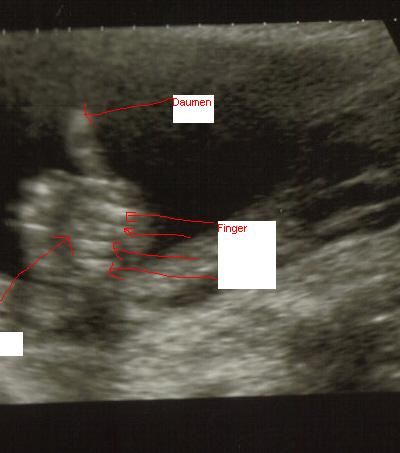

Meine Tochter Ultraschall vom 24.9.07